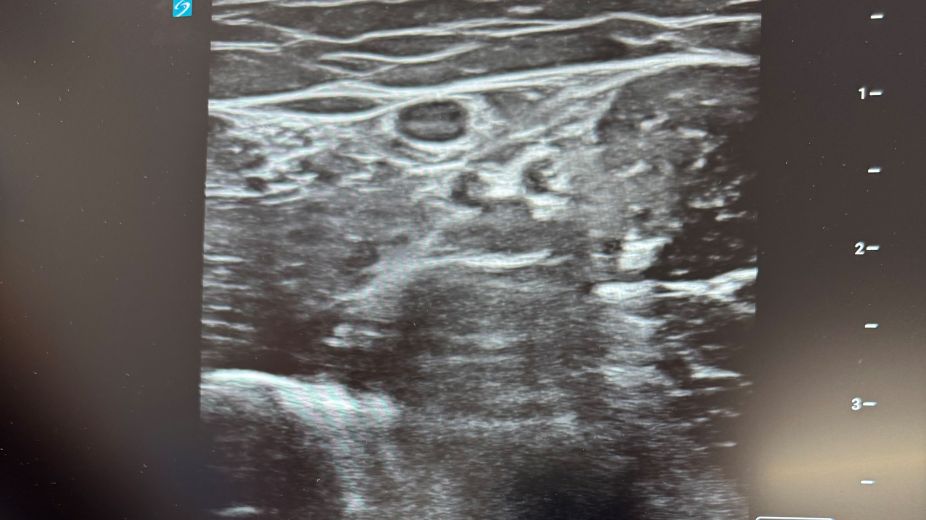

Ultrasound machine for Ward 16 at York Hospital

York & Scarborough Hospitals Charity recently funded an ultrasound machine for Ward 16 at York Hospital. The surgical ward previously shared an ultrasound machine with theatres. The medical staff and Surgical Care Practitioners use ultrasound devices for insertion of a midline catheter which is a thin, flexible, hollow tube. They can be described as a long cannula. One end of the catheter is fixed to just above the crease of your elbow. This enables trained staff to administer medication into the patient’s vein, without the need for repeated cannulations and can stay in place for approximately four weeks. The ultrasound can also be used for difficult canulations and blooding taking on the ward.

Purchasing the device will mean that midlines can be done on the ward instead of patients being taken into theatre. It will cut down the number of patients in theatre and will lead to better and more efficient patient care as this will reduce delays for treatment.